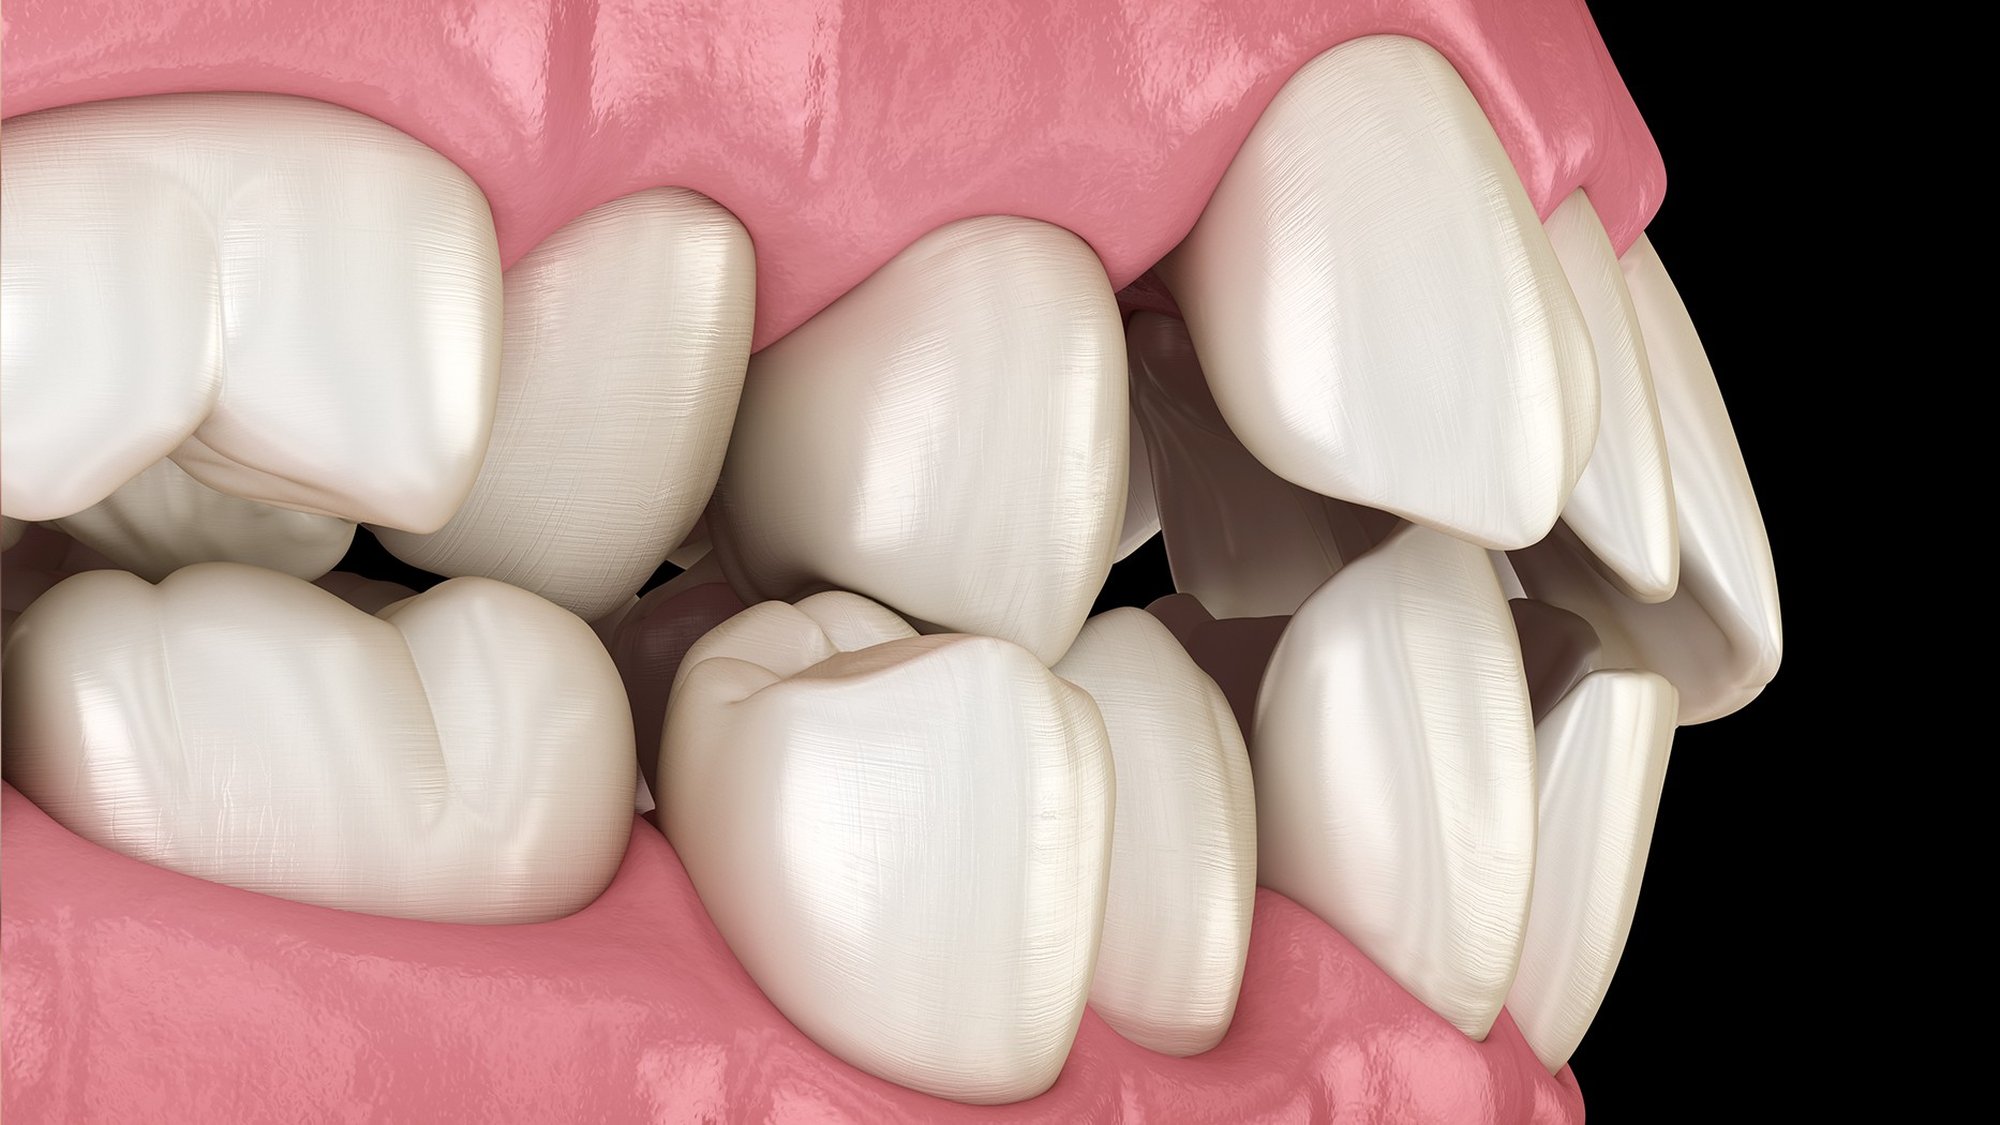

Altıncı yaştan itibaren çocukların hem süt dişleri hem de kalıcı dişleri çıkmaya hazırdır. Bütün kalıcı dişler çıktığı zaman, diş çıkarma süreci tamamlanır. Düşen ya da kırılan dişlerin yerine yenisi çıkmaz. Yine de bilim insanları, dişleri yeniden çıkarmanın yollarını aramaktadır.[2]